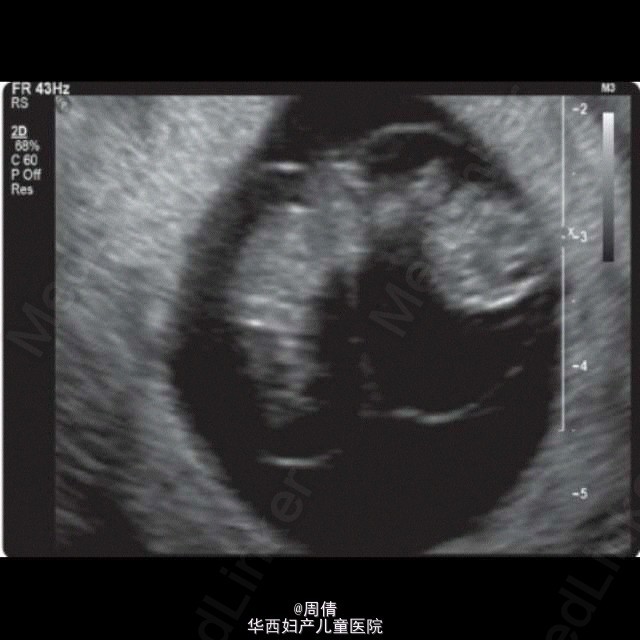

超声诊断单绒毛膜双胎羊膜囊融合一例

37岁女性,G3P1,自然受孕9w。 阴道超声示:子宫腔单个妊娠囊内2个胎儿,单绒毛膜。拥有共同的卵黄囊,在脐周相互连接。